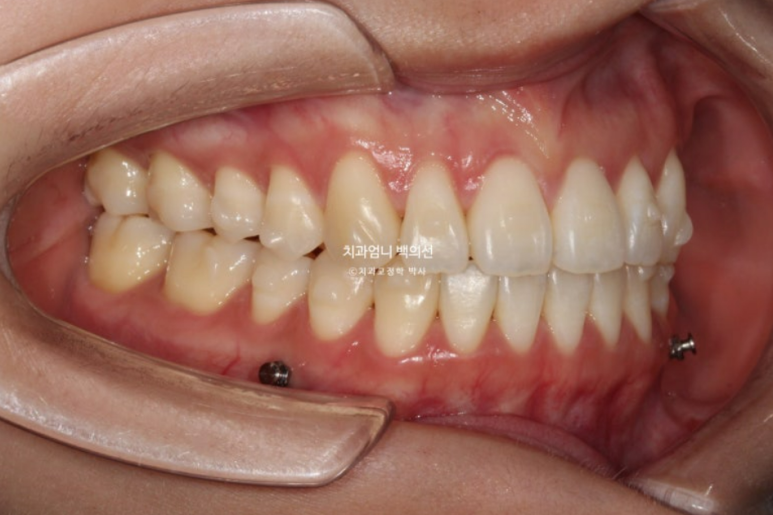

25년 4월 치료를 마무리 했습니다. 중심선은 이제 정확히 맞습니다.

철사유지장치 부착 후 환자분은 가철식 유지장치로 비베라를 선택했는데 비베라 제작을 기다리는 2주동안 사진상 메탈고리와 하악 미니스크류 사이에 고무줄을 걸면서 초진시 떠있던 해당치아의 교합을 유지합니다.

처음에 들려있던 치아라 철사유지장치 부착 후 아무 장치도 안 끼기 시작하면 재발에 의해 미세하게 다시 들리기 때문입니다.

어금니 교합은 좋습니다.

이제 전 후 비교 보겠습니다.

23.11~25.04

이제 어금니 함입에 의한 하악골 자가회전 효과를 보겠습니다.

실눈 뜨고 보면 처음에 비해 하관이 약간 짧아지며 턱끝이 약간 나오고 도툼해졌습니다.

발치했으면 큰일날 뻔했습니다.